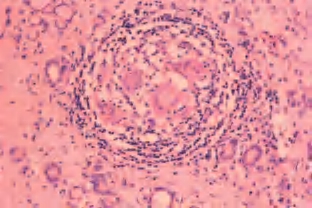

2.镜下 甲状腺部分滤泡破坏,溢出的胶质周围有组织细胞和多核巨细胞包绕,形成肉芽肿,但无干酪样坏死。间质可见多量嗜酸性粒细胞、淋巴细胞和浆细胞浸润。愈合期表现为滤泡上皮再生、间质纤维化及瘢痕形成(图3-27、图3-28)。

图3-27 亚急性肉芽肿性甲状腺炎